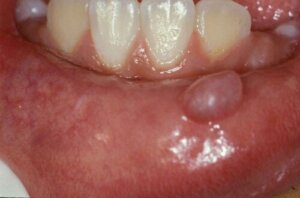

Mukosel şu anda insan ağzındaki en yaygın iyi huylu lezyon olarak kabul edilmektedir. Küçük tükürük bezlerinin olduğu bölgelerde oluşan mukusla dolu küçük bir kistten başka bir şey değildir. Araştırmalar, mukosellerin %96’sının alt dudaktan kaynaklandığını tahmin ediyor.

Minör tükürük bezlerindeki bir bozukluktan kaynaklanan iyi huylu kistik lezyonlardır. Genellikle mukus içerirler ve mukus hücreleri ile kaplıdırlar. Yüzeysel veya derin olabilirler ve boyutları birkaç milimetreden 3 santimetreye kadar değişebilir.

Mukosel, ağzın içinde, genellikle alt dudakta, mukusla dolu küçük bir kabarcık veya nodül olarak aniden kendini gösterir. Yarı saydam mavi renkte olabilir veya alttaki mukozanın aynı tonunu koruyabilir. Bir yara eşlik etmedikçe ağrısızdırlar.

Bazı insanlar genellikle onları aftlarla karıştırır. Bununla birlikte, ikincisi, ağrı ve rahatsızlık üreten kırmızımsı kenarlara ve beyaz merkezlere sahip ülseratif lezyonlardır. Alt dudak en sık yerleşim yeri olmakla birlikte dil, damak, yanak mukozası ve ağız tabanında da oluşabilir.